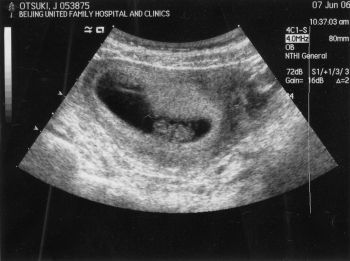

| 2006-08-23 北京渡航前に | 2006-09-09 北京にて(横顔くっきり!) | |